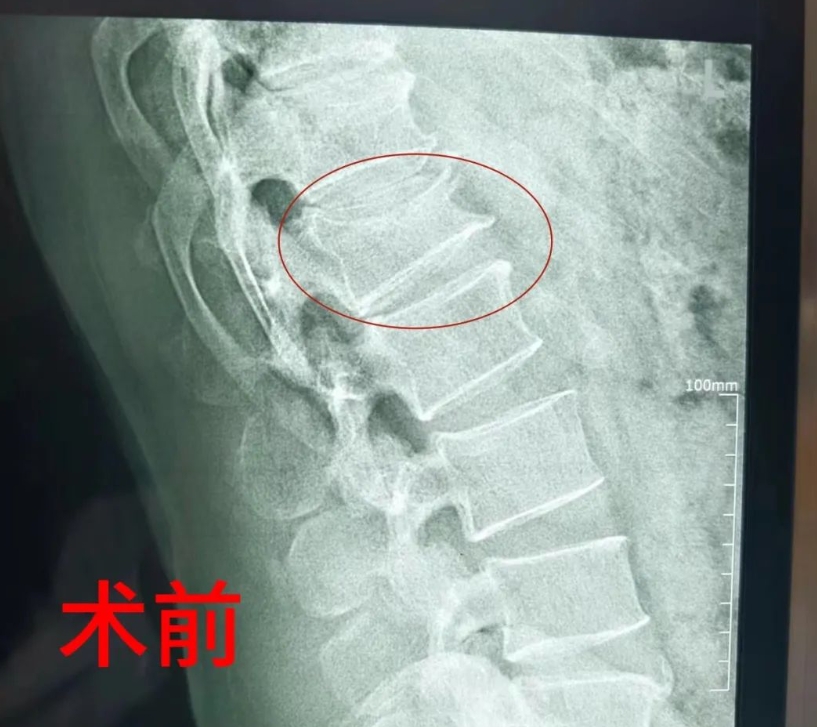

原来,患者为腰1椎体压缩性骨折,进一步完善核磁共振检查还提示,患者还合并有胸12椎体、胸7椎体骨折。经创伤外科仔细评估,因患者腰1椎体压缩已超过三分之一,手术指征明确。为了确保手术效果,考虑到患者体重高达190多斤,属于超重范畴,常规大切口手术可能导致术中切口较长、软组织剥离过多、出血过多以及术后恢复缓慢,并且容易合并伤口液化、感染等风险。

因此,创伤外科团队最终决定为患者选择胸腰椎骨折微创钉棒固定术。手术过程顺利,患者的椎弓根螺钉及所有螺钉均精准植入椎弓根内,钉子长短粗细恰到好处。术后复查结果显示,患者手术切口愈合良好,完全恢复。